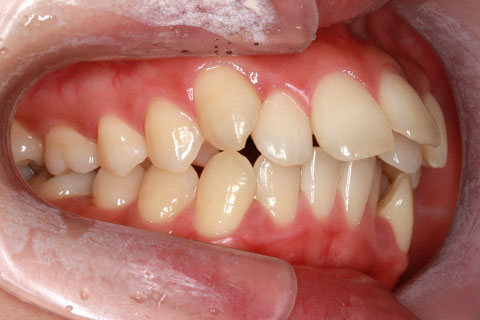

フルリンガル矯正2(上下の歯を舌側矯正で治療)

治療前

治療中

治療後

- 年齢・性別

- 42歳男性

- 治療期間

- 1年6ヶ月

- 抜歯

- なし

- 治療費

- 120万円(税込み)

- 備考

- マルチブラケットを用いた矯正治療

- 治療内容

- 反対咬合をフルリンガル矯正治療にて改善

- 施術の副作用(リスク)

- 表側矯正と比較して、歯根の角度を確立する「トルク」の力がかかりにくい。